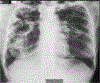

Methods: We consecutively enrolled participants with PTB with persistent pulmonary symptoms after 2 months of anti-TB treatment at Mulago Hospital, Kampala, Uganda, between July 2020 and June 2021. CPA was defined as a positive Aspergillus-specific IgG/IgM immunochromatographic test (ICT), a cavity with or without a fungal ball on chest X-ray (CXR), and compatible symptoms >3 months.

Results: We enrolled 162 participants (median age 30 years; IQR: 25-40), 97 (59.9%) were male, 48 (29.6%) were HIV-infected and 15 (9.3%) had prior PTB. Thirty-eight (23.4%) sputum samples grew A. niger and 13 (8.0%) A. fumigatus species complexes. Six (3.7%) participants had intracavitary fungal balls and 52 (32.1%) had cavities. Overall, 32 (19.8%) participants had CPA. CPA was associated with prior PTB (adjusted odds ratio [aOR]: 6.61, 95% CI: 1.85-23.9, p = .004), and far advanced CXR changes (aOR: 4.26, 95% CI: 1.72-10.52, p = .002). The Aspergillus IgG/IgM ICT was positive in 10 (31.3%) participants with CPA.